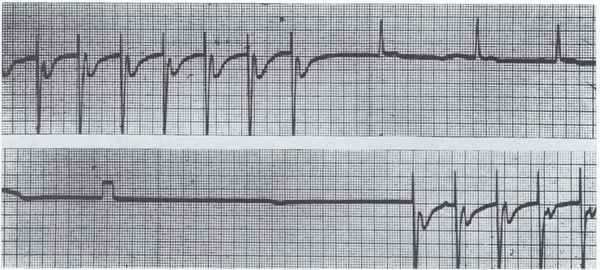

1952年11月13日

Paul Zoll给一组心脏骤停的病人安装了一个新型的体外起搏装置,避免了痛苦的开胸心脏按摩。

1956年

此前,急性心肌梗塞的诊断依赖于心电图,这导致很多病人被漏诊了。血清标志物,例如白细胞计数和红细胞沉降率等指标也在使用,但都不够特异。S.J. Adelstein和同事发现急性心梗患者锌浓度下降,乳酸脱氢酶和苹果酸脱氢酶的浓度上升。其中乳酸脱氢酶的表现尤为突出,这使得血清标志物诊断急性心梗成为可能,加速了临床诊断并且使诊断更加精确。